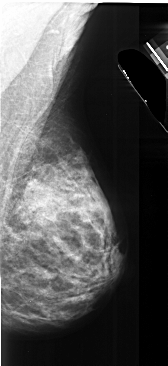

A_1027_1.RIGHT_MLO

RIGHT_MLO LINES 5476 PIXELS_PER_LINE 2506 BITS_PER_PIXEL 16 RESOLUTION 42 NON_OVERLAY